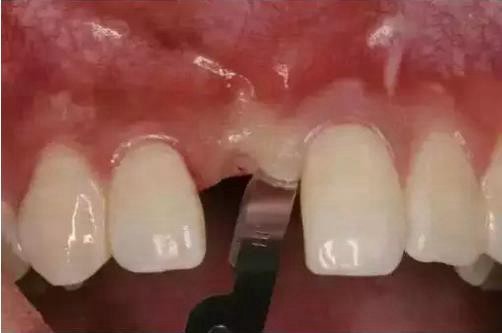

第一步:牙槽嵴頂切口,以執(zhí)筆式持手術(shù)刀,切開前須找一個(gè)可靠的支點(diǎn),多以余留牙為支點(diǎn),運(yùn)刀時(shí)必須做到穩(wěn)和準(zhǔn)(圖)。對于牙齦覆蓋區(qū)域或者牙槽骨面較平整的牙槽黏膜覆蓋區(qū)域,可以一刀切至骨膜下,對于牙槽骨表面不平整的牙槽黏膜覆蓋區(qū)域,可以分兩次切開,先切開黏膜表層,然后再切至骨膜下,此種方式的優(yōu)點(diǎn)是容易做到切緣整齊,且準(zhǔn)確、層次清晰。

第二步:齦溝內(nèi)切口,從齦溝內(nèi)插入,直達(dá)牙槽嵴頂,緊貼牙面運(yùn)刀,不可傷及游離齦緣。分離要完全,以免翻瓣時(shí)造成牙齦撕裂。

第三步:行縱向切口,從齦溝底向齦緣運(yùn)刀,避開牙齦乳頭,止于軸面角,形成外斜切口(圖)。